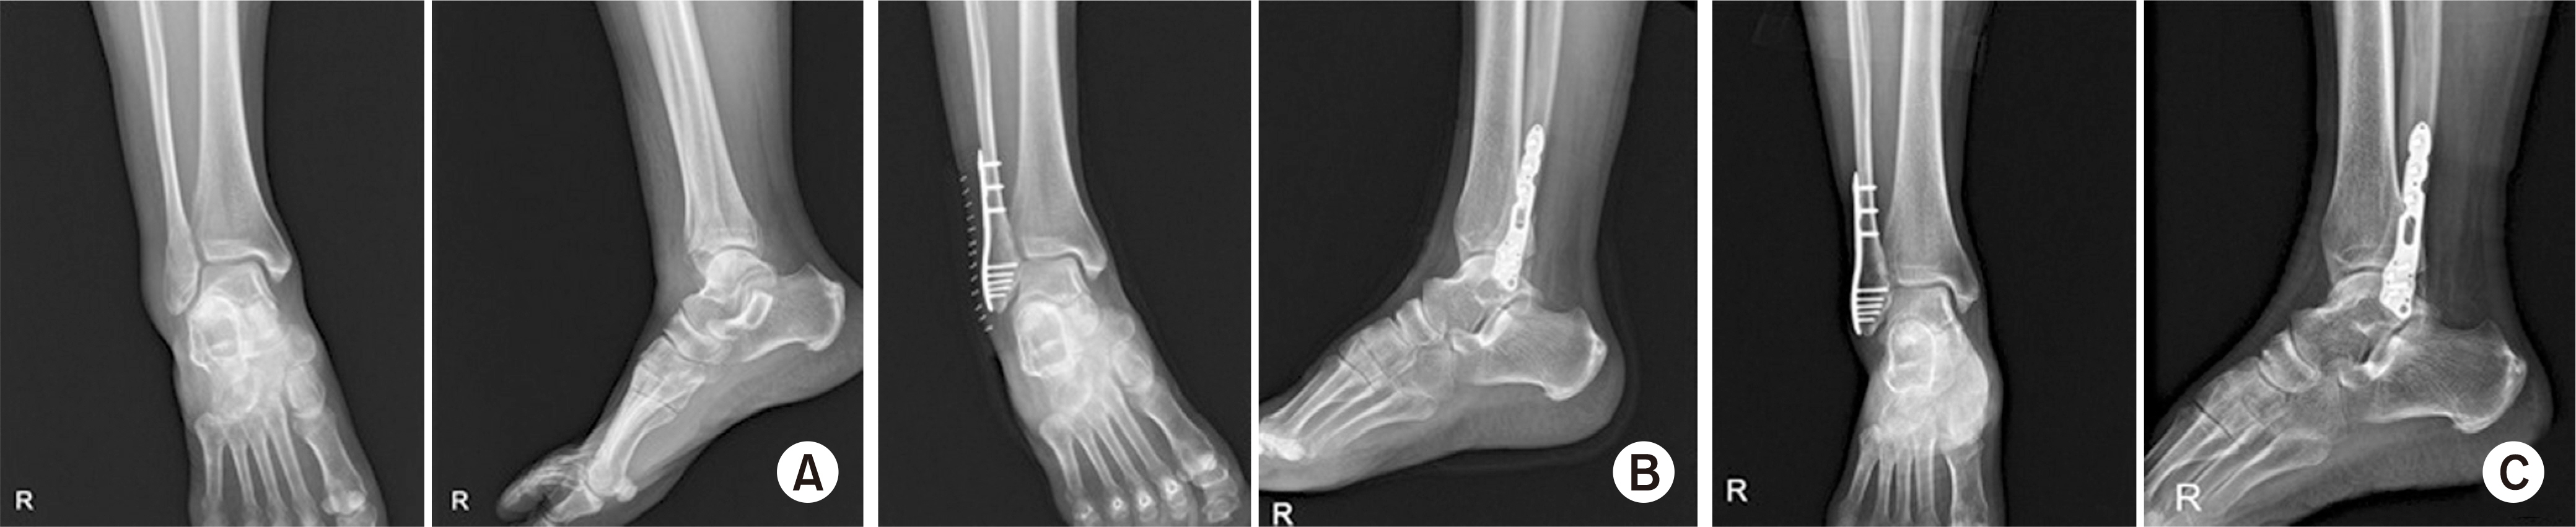

Fig. 1.

(A) A 54-year-old female patient was diagnosed with isolated lateral malleolar fracture according to the simple radiography. (B) Surgical fixation with locking-plate screw on the postoperative radiography. (C) Bone-union was achieved within 12 months of surgery.